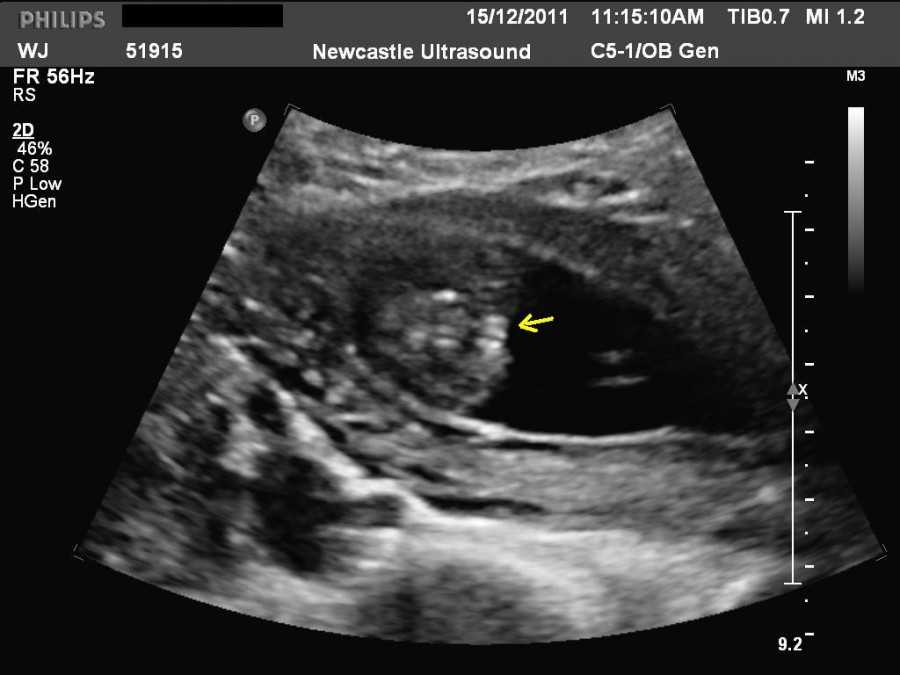

Также показано ультразвуковое исследование плода. Процедура УЗИ позволяет определить срок беременности, толщину плаценты, а также общее состояние яичников и пуповины.

УЗИ на 9-ой неделе беременности

На УЗИ плода на 9 неделе определяется толщина плаценты и общее состояние пуповины. При помощи допплера, будущая мама может отметить частоту сердечных сокращений малыша. Хотя многие внутренние органы уже достаточно развиты, это не всегда можно увидеть на УЗИ на 9 неделе.

Внутренние органы крохи еще могут выступать в виде пупочной грыжи, но нет повода для беспокойства, ведь это совершенно нормальное явление.

На УЗИ на данном сроке обязательным является общая оценка состояния яичников.

УЗИ на сроке 9 недель